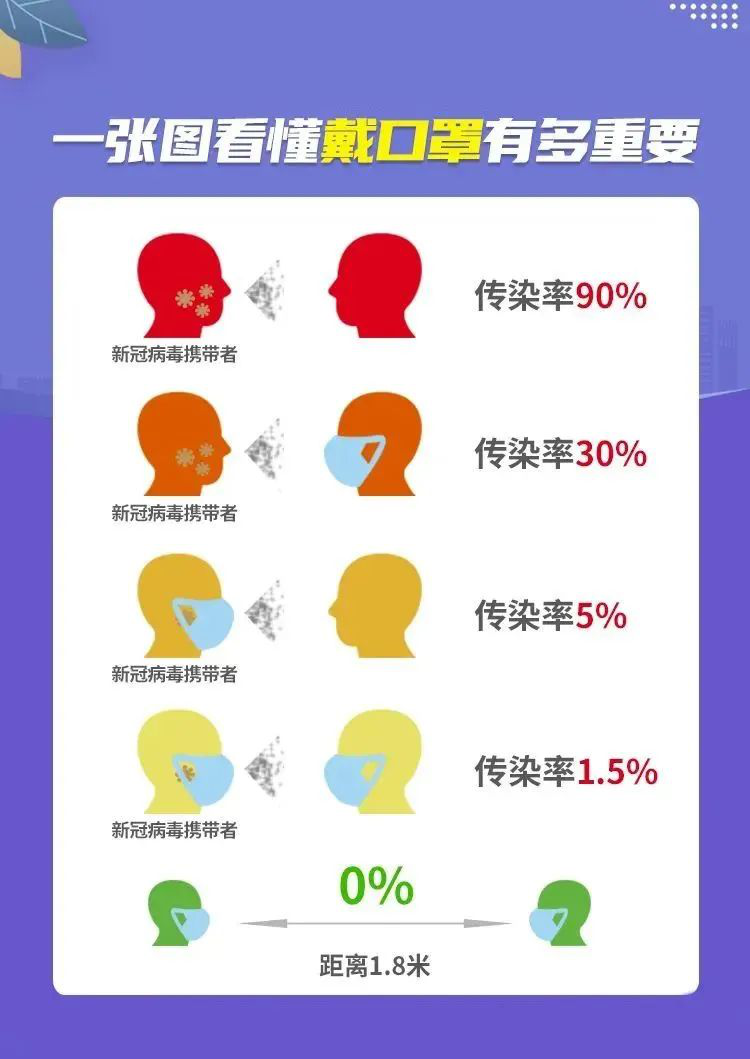

有研究显示,只要双方都佩戴口罩且间隔1米以上,造成感染的几率几乎为0。

新冠病毒携带者与没受感染人群交往中戴口罩与不戴口罩的传染率区别:

上图表明,人们在日常交往中,如果都科学规范佩戴口罩,病毒传染率极低。戴口罩不仅对自己有利,对他人也有好处,不仅是保护自己,也是对他人负责。